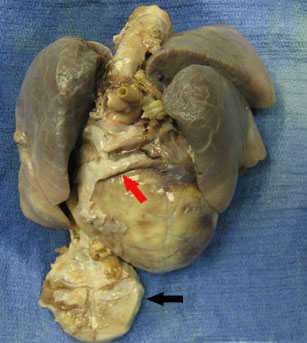

At the time of autopsy, a cardiac pacemaker was identified with leads attached to the right atrial and ventricular walls externally. The heart was globular and enlarged and the epicardial surface, underlying the pacer leads, was irregular and firm (Figure 1). There was left ventricular hypertrophy with left ventricular dilatation. The coronary arteries demonstrated right dominance with no plaques or obstructions. The endocardial surfaces were without lesion. The foramen ovale was closed and no valvular abnormalities were identified.

Figure 1: Heart and lung block demonstrating enlarged, globular heart and pacer (black arrow) encased in fibrous tissue. White fibrous tissue is also present overlying the pacer leads (red arrow).